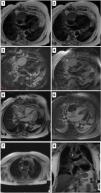

A 71-year-old woman was hospitalized for an unexplained fever. A positron emission tomography using PET-18FDG showed increased and diffuse uptake in the pericardium. An MRI revealed a small circumferential pericardial effusion and slight pericardial thickening over the right lateral side of the heart (Video 1, CINE sequences). The patient was discharged after the fever resolved. Some months later, she started having symptoms of exertional dyspnea and a dry cough. A CT raised concerns about a pericardial mass and multiple adenopathies. Reassessment by MRI showed a cardiac mass (84 mm×48 mm) with irregular borders in the right atrioventricular sulcus extending throughout the free wall of the right atrium (Video 2, CINE sequences). It was isointense on T1 (Panel, Image 1) and T2 (Panel, Image 2), hyperintense on T2 STIR (Panel, Image 3), and did not saturate in the fat saturation sequences (Panel, Image 4). It perfused on the first contrast passage (Video 2, perfusion sequences), with hypointense foci on early enhancement sequences (Panel, Image 5) and with a heterogeneous appearance on late enhancement sequences (Panel, Image 6). Exuberant adenopathy conglomerates were observed (Panel, Images 7 and 8, asterisk). A biopsy of an axillary lymph node revealed diffuse large B-cell lymphoma and chemotherapy was started.

Panel exhibiting the cardiac mass characteristics on cardiac magnetic resonance imaging sequences. Image 1: T1 sequence. Image 2: T2 sequence. Image 3: T2 STIR sequence. Image 4: Fat saturation sequences. Image 5: Early enhancement sequence. Image 6: Late enhancement sequences. Images 7 and 8: Exuberant adenopathy conglomerates highlighted with an asterisk.